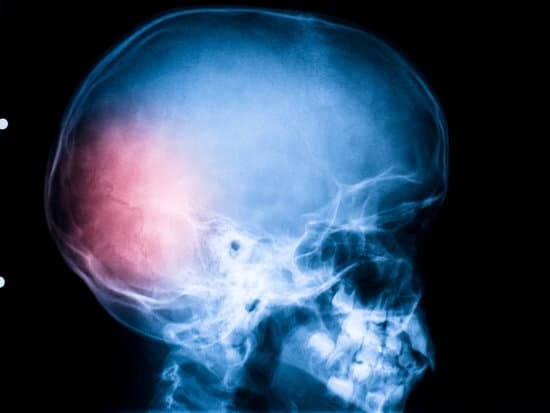

두부 외상 수술은 머리에 발생한 심각한 손상(두부 외상)을 치료하기 위해 시행되는 외과적 수술입니다.

두부 외상은 교통사고, 낙상, 폭력 등 다양한 외부 요인으로 인해 발생할 수 있으며, 두개골 골절, 뇌출혈, 뇌진탕, 뇌부종 등을 유발할 수 있습니다.

뇌 CT 스캔이나 MRI를 통해 뇌 손상 여부와 출혈의 위치 및 정도를 정확히 진단합니다.